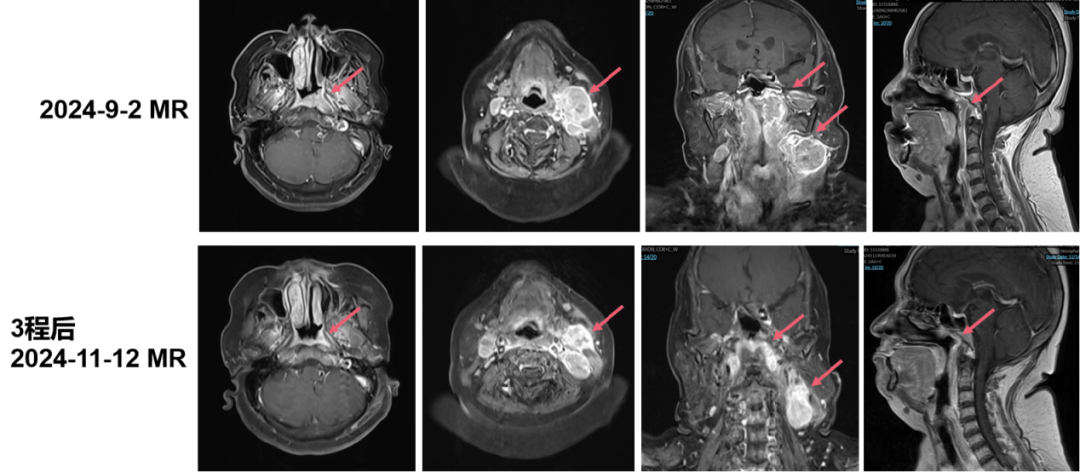

• 影像学检查(2024年11月12日 鼻咽部+颈部MR):鼻咽癌黏膜增厚较前减轻,左侧咽隐窝肿块较前缩小。双侧咽后间隙及双侧颈部多发淋巴结转移,右侧咽后间隙淋巴结较前新发,原左侧Ⅱ区较大淋巴结较前缩小,余双颈淋巴结多数较前增大。

2025423复查MRI疗效评价为CR血浆EBV-DNA为0 copies/mL

image.png

本病例展示了一例Ⅲ期鼻咽癌患者的临床治疗过程与转归。患者初始接受三周期“白蛋白紫杉醇+顺铂+特瑞普利单抗”方案治疗,后续影像学评估显示,原发灶虽有一定程度缩小,但“右侧咽后间隙淋巴结较前新发,双颈淋巴结多数较前增大(除左侧Ⅱ区较大淋巴结外)”。这提示PD-1抑制剂联合化疗方案未能有效控制疾病进展,临床需迅速调整治疗策略。

面对此不利局面,治疗团队基于对艾托组合抗体作用机制及临床应答特征的深入理解,于第四周期将治疗方案调整为艾托组合抗体联合化疗,并后续同步放疗。值得强调的是,该方案迅速展现出卓越疗效:淋巴结明显消退疗效评价达到CR,且血浆EBV-DNA持续降至0拷贝——这标志着肿瘤在影像学和分子学层面均实现了深度清除。尤为重要的是,本病例整个治疗过程中安全性表现优异,在全程使用艾托组合抗体的情况下,未出现新增的、高级别的免疫相关不良事件,这充分表明艾托组合抗体与放化疗的联合策略在临床应用中具备优异的安全性与耐受性,为全程规范治疗提供了重要保障。